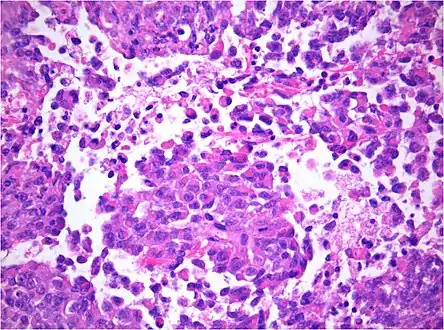

AT/RT and rhabdoid tumor share the term "rhabdoid" because under a microscope, both tumors resemble rhabdomyosarcoma.

AT/RT Histology with numerous rhabdoid tumor cells

Rhabdoid Tumor Cell - 400X Magnification

Histology

The tumor histopathology is jumbled small and large cells. The tissue of this tumor contains many different types of cells including the rhabdoid cells, large spindled cells, epithelial and mesenchymal cells, and areas resembling primitive neuroectodermal tumor (PNET). As much as 70% of the tumor may be made up of PNET-like cells. Ultrastructure characteristic whorls of intermediate filaments are seen in the rhabdoid tumors (as with rhabdoid tumors in any area of the body). Ho and associates found sickle-shaped embracing cells, previously unreported, in all of 11 cases of AT/RT.[16]